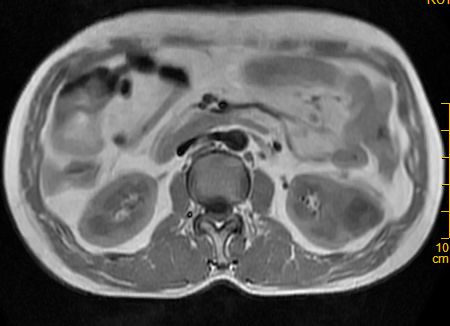

标题: MRI2883:左肾占位性病灶,请大家来会诊!

左肾占位性病灶,请大家来会诊!

考虑多发囊肿融合

肾癌

多囊性肾瘤

考虑 1囊性肾癌 2多囊性肾瘤。

考虑左肾囊性肾癌,多囊性肾瘤待排。

考虑左肾囊性肾癌,多囊性肾瘤待排。建议增强。

左肾癌囊变。

左肾复杂性外生囊肿,错构瘤待排。